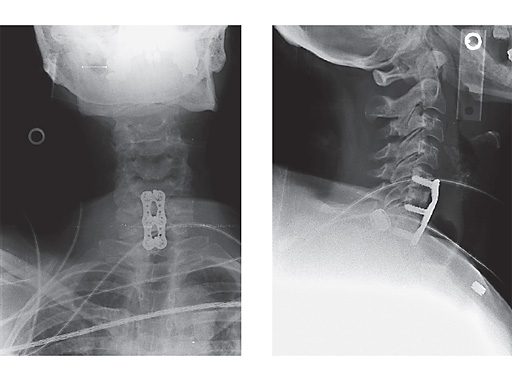

Postoperative x-rays of a case treated with Vectra in which this 60-year-old female underwent discectomy and interbody grafting for C56, 67 stenosis with radiculopathy.